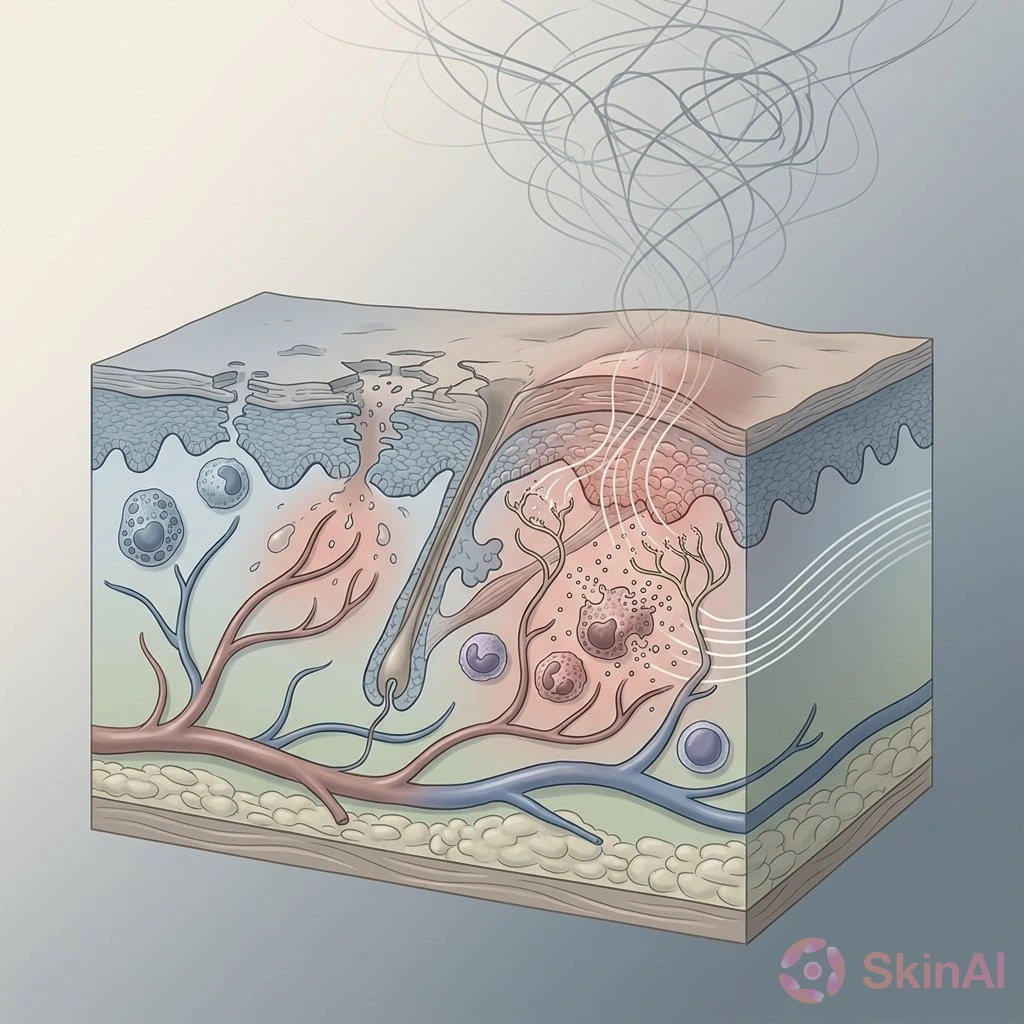

Chronic Spontaneous Urticaria Impacts Mental Health and Quality of Life

Discover how chronic spontaneous urticaria affects mental health, causing anxiety, depression, and sleep issues, and why holistic care is essential.